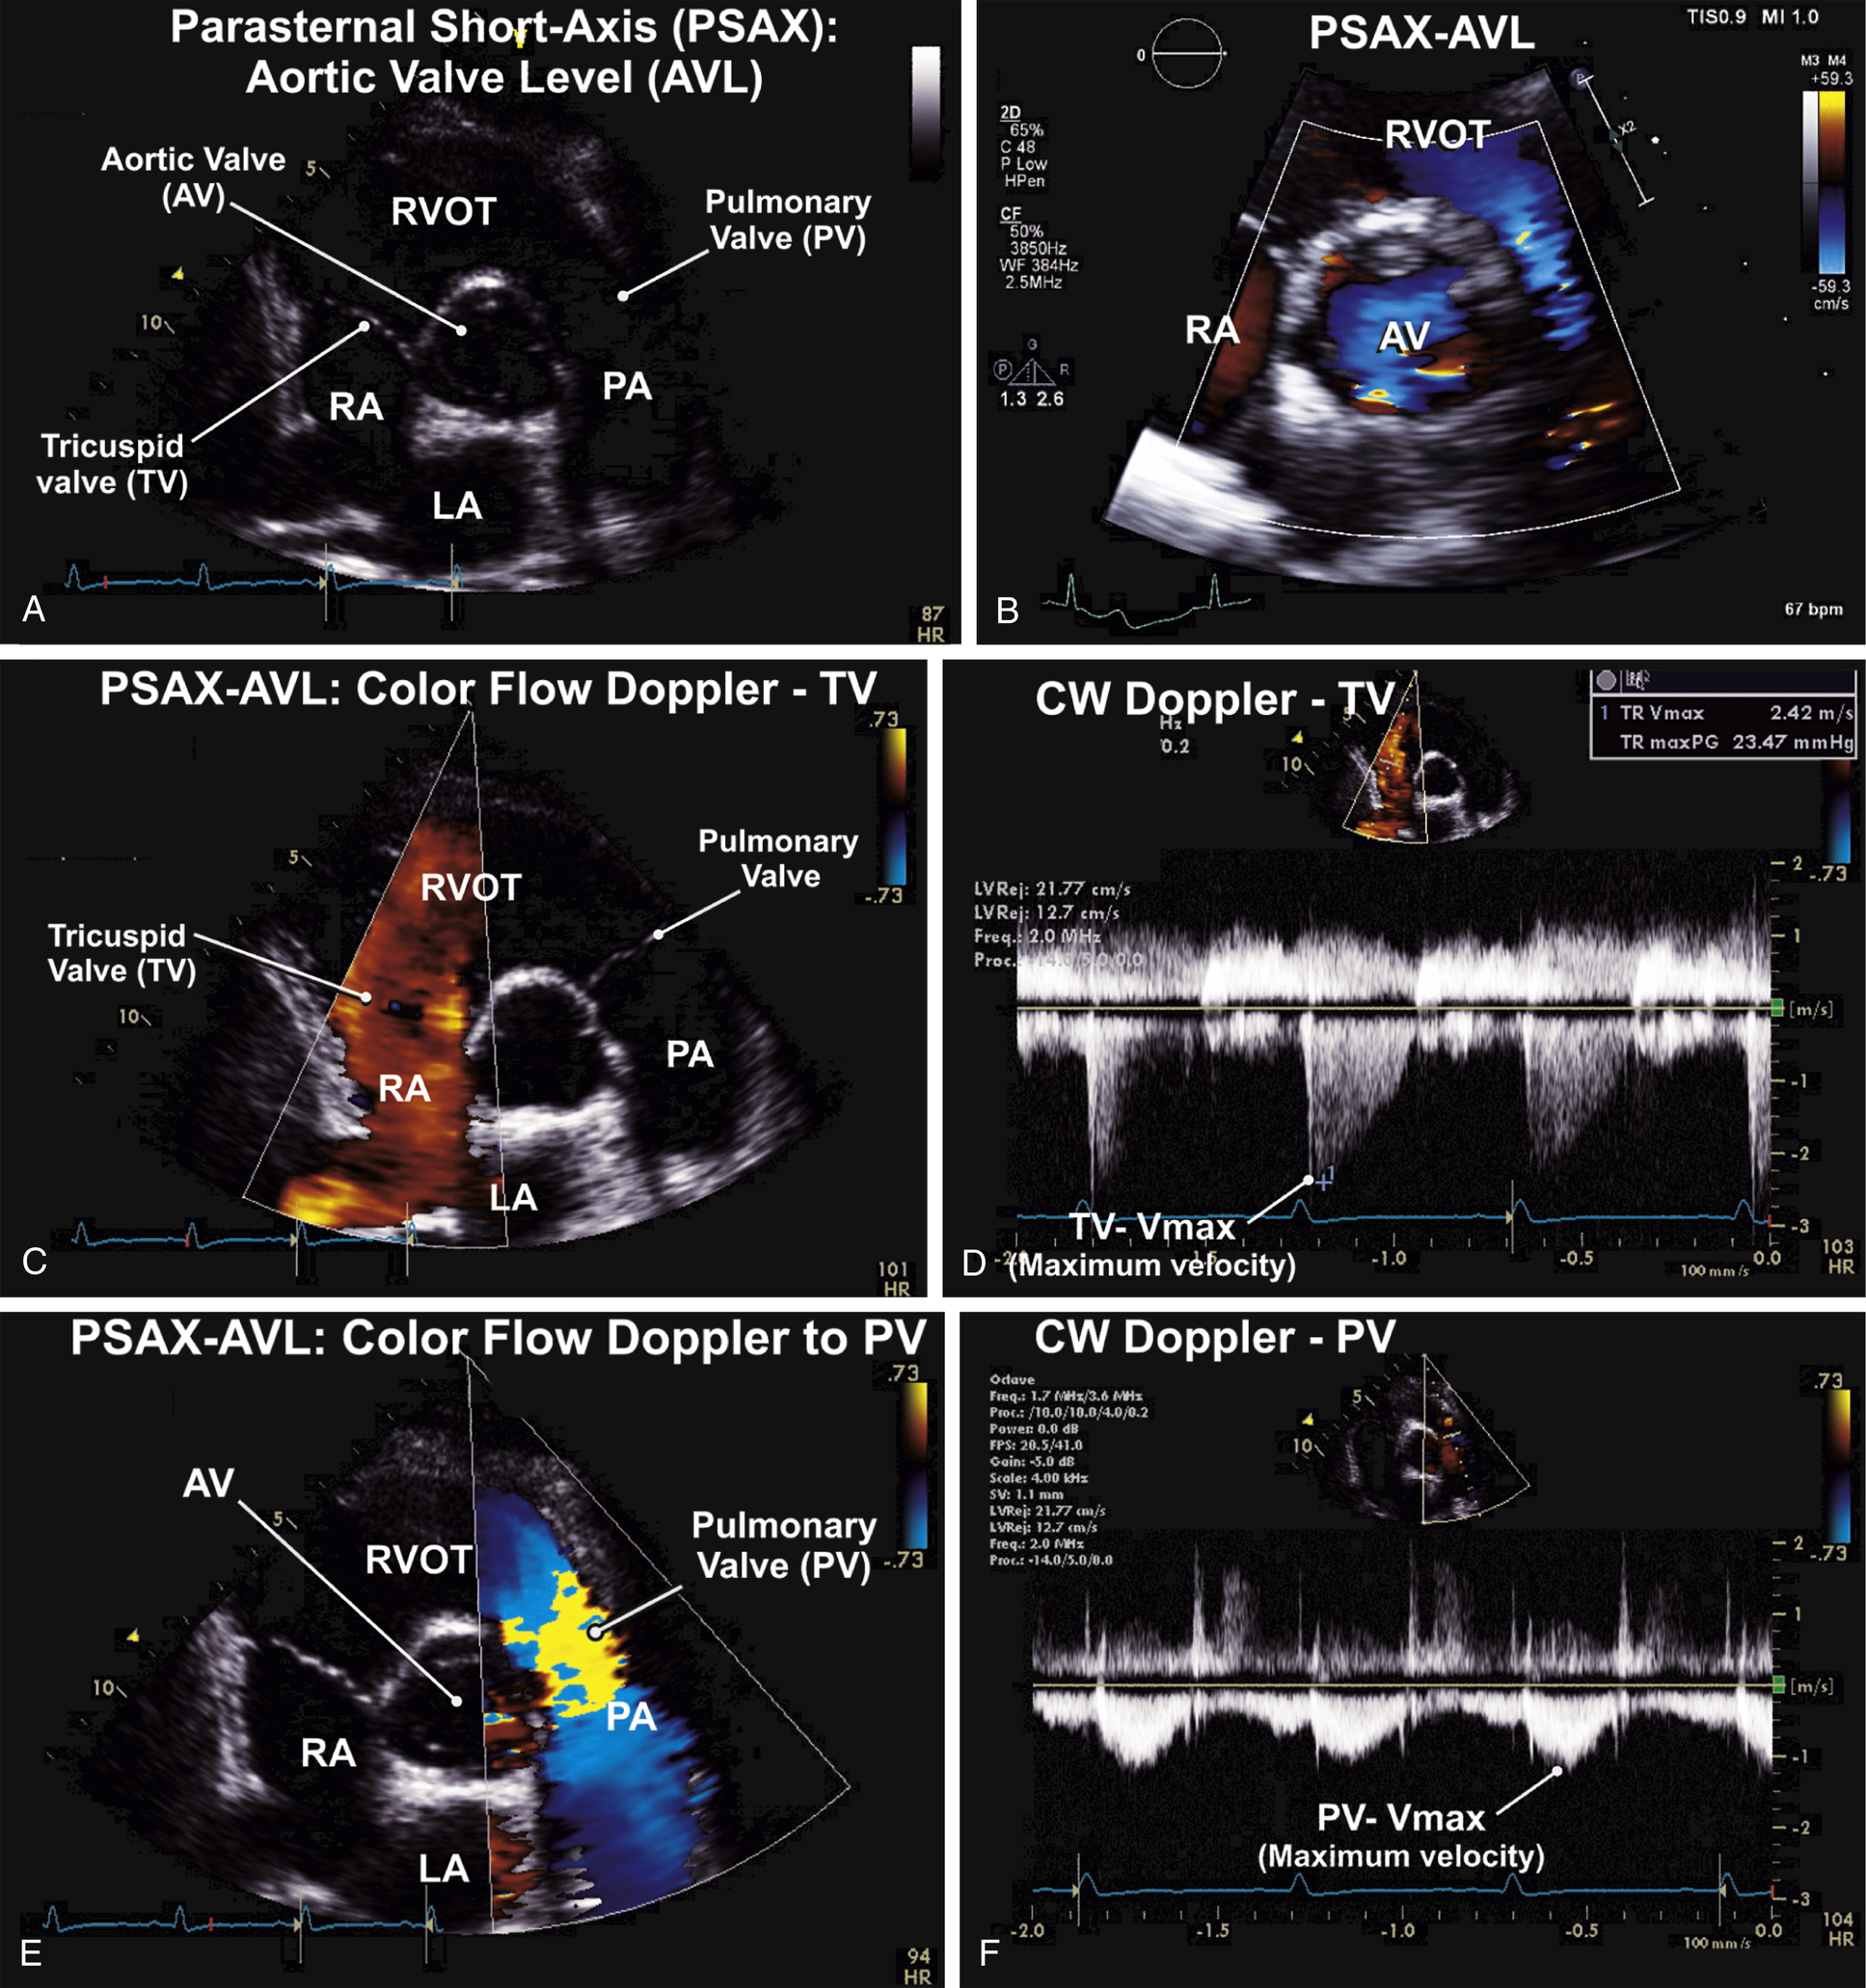

| P | Short-axis (SAX) | Aortic valve level: AV, TV, PV, IAS, LA, IAS, coronary arteries; IVC |

TABLE 9.3

Parasternal Short-Axis Views: Normal Examination (see Figs. 9.3 and 9.4)

| Transducer Position (Window) | 2D ± M-MODE ± 3D | CFD | Spectral Doppler PW, CW |

| Parasternal short-axis (PSAX): aortic valve level (AVL) | 2D to PV M-mode (optional) 3D full-volume (optional) | CFD to AV CFD to TV for TR CFD to PV for PR | CW to TR max velocity |